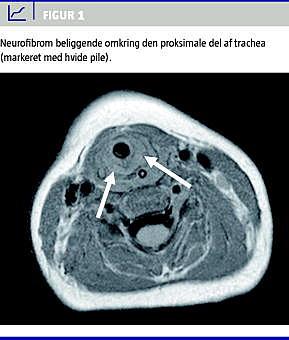

Dagen efter overflytningen blev der foretaget laryngoskopi, trakeoskopi og øsofagoskopi i generel anæstesi. Man fandt en rumopfyldende bløddelsproces beliggende i venstre bageste del af larynx og den proksimale del af trachea. Processen var ca. to en halv centimeter lang. En computertomografi viste en ca. to centimeter lang subglottisk homogen ringformet struktur om trachea (Figur 1 ). På baggrund af dels kliniske fund og dels fund ved skanningen blev der taget biopsier fra det subglottiske område. Patologisvaret viste pleksiformt neurofibrom. Tumoren infiltrerede både larynx, den proksimale del af trachea og hypopharynx. Radikal kirurgi var derfor ikke mulig. Da barnets respiratoriske situation var uholdbar, blev han trakeotomeret. Efterfølgende har han ikke haft respirationsproblemer. Han blev fulgt med magnetisk resonans-skanninger af cerebrum, hals og thorax hvert halve år. Frem til opgørelsestidspunktet havde der ikke været progression af det laryngeale neurofibrom.